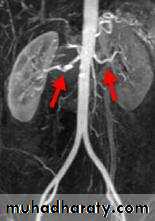

Angiogram or MRIA.

Both kidneys are asymmetrical in their size .

may reveal a discrepancy in size between the two kidneys.(small size kidney).